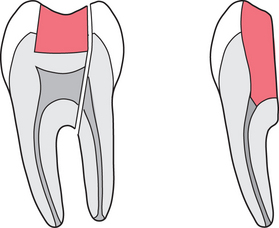

eliminate the ‘apical delta’ of minor root canals that cannot be effectively sealed by conventional endodontics (Fig. 6.1)

Fig. 6.1 The apical delta of root canals is a potential area for leakage despite conventional endodontics. Apicectomy aims to minimize leakage at this site.